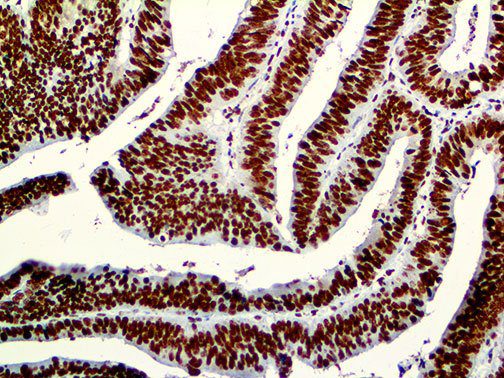

The first cytokines released are interleukin 1β (IL-1β) and tumor necrosis factor-α (TNF-α), which attract a variety of circulating white blood cells (WBCs) to the infection site, including neutrophils, monocytes, macrophages, and natural killer (NK) cells. This response, along with the antipathogenic chemicals released by these cells (i.e., complement), comprise the innate immune response. These cells directly attack the invading pathogen and also release additional cytokines, chief among them interleukin-1 and 6 (IL-6). IL-6 is essential for invoking the adaptive immune response, which calls T-cells, B-cells, and T helper (Th) cells to the infection site. IL-6 also stimulates further recruitment, proliferation and activation of macrophages.

This activation induces inflammatory monocytes to highly express IL-6, starting a localized and then systemic cascade effect that results in hyperproduction of IL-6, which accelerates the inflammatory process. Because IL-6 also increases vascular permeability, excessive levels cause blood vessels to become very leaky. This, along with clotting factors released from vascular endothelial cells, stimulates the coagulation cascade, resulting in microthrombosis (tiny clots), which leads to ischemia and tissue death of the kidney, intestines, heart, liver, brain and extremities.